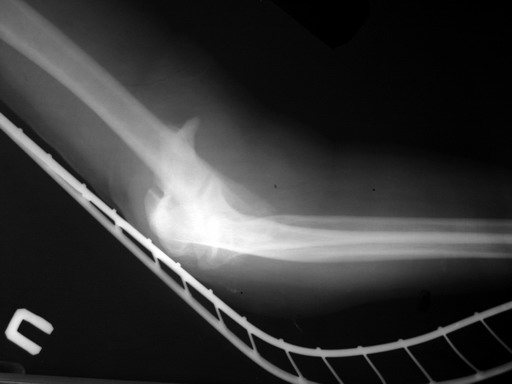

Alexander Artemiev 14 Сентябрь 2005, 16:19

Женщина 42 лет, операция через неделю после перелома.

Д-з - открытый перелом мыщелков со смещзением и локтевой кости

без смещения - падение с лошади.

До операции снимки не очень, тем более в гипсе.

Остеосинтез закрытый (если так можно выразиться), т.е. без

разрезов. Длительность операции - около 1,5 часа со студентом.

6 щелчков ЭОПом.